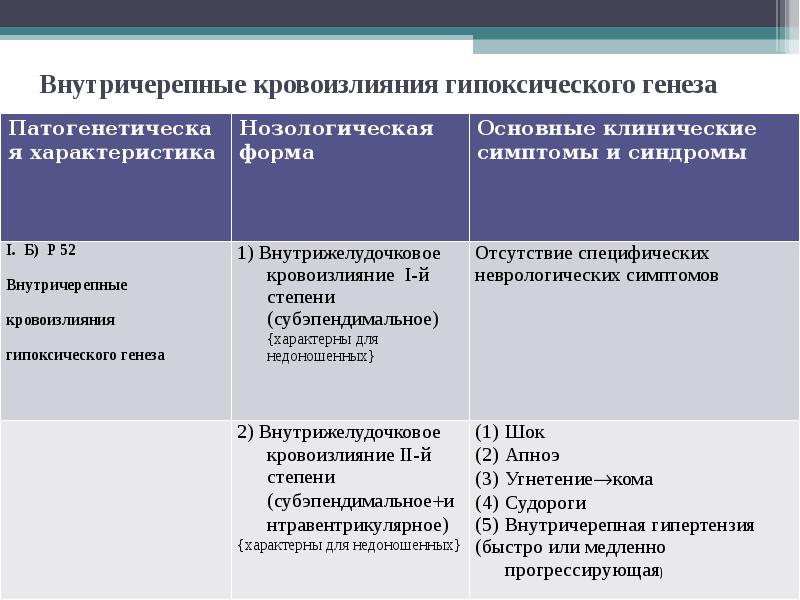

Внутричерепные кровоизлияния у новорожденных презентация - 92 фото